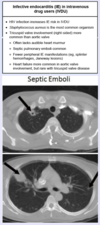

One symptom associated with bacterial endocarditis is septic arterial or pulmonary […].

One symptom associated with bacterial endocarditis is septic arterial or pulmonary emboli.

mnemonic: FROM JANE; may cause various nodes/lesions associated with bacterial endocarditis

mnemonic: FROM JANE; occurs due to embolization of septic vegetations